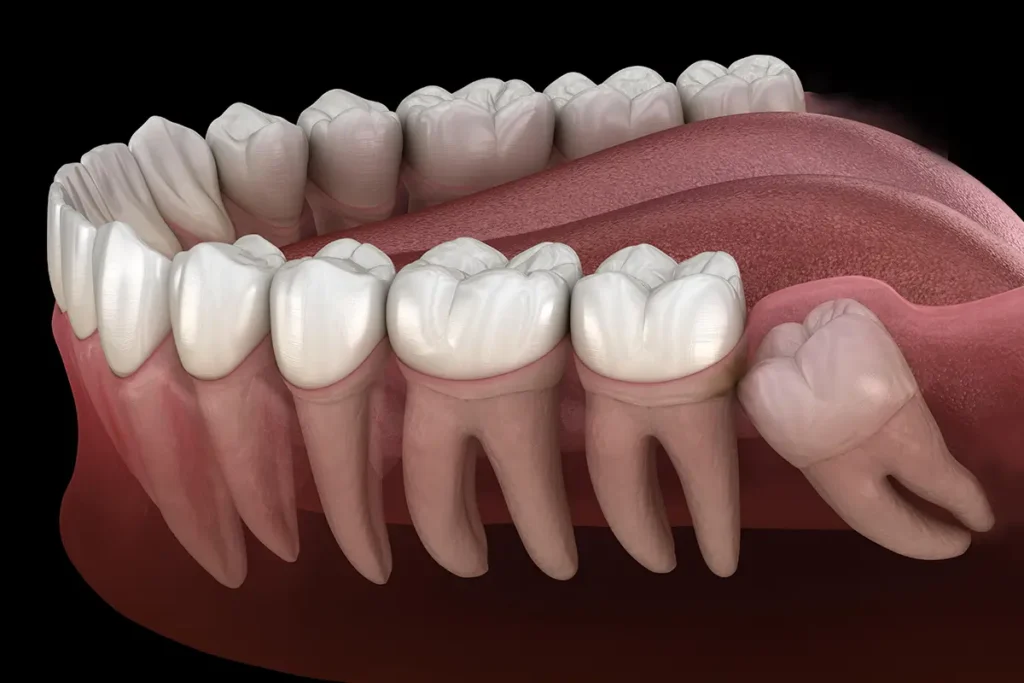

Wisdom teeth, also known as third molars, usually emerge between the ages of 15 to 35. While some people experience no issues, many experience pain, swelling, and infection due to lack of space in the jaw. This often results in impacted or partially erupted wisdom teeth, which can affect neighboring teeth and gums. At Savani Dental Clinic, we specialize in safe, comfortable wisdom tooth removal procedures tailored to your unique dental needs. Whether it’s a straightforward extraction or a more complex surgical case, you’re in expert hands.

Some wisdom teeth are deeply impacted or lie at awkward angles. In such cases, simple extraction isn’t enough, surgical tooth removal becomes necessary. This procedure involves a small incision in the gum to access and remove the tooth safely. At Savani Dental Clinic, we use advanced imaging, minimally invasive techniques, and the latest dental technology to ensure: